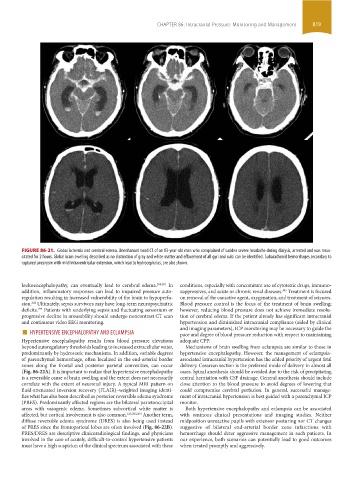

FIGURE 86-21. Global ischemia and cerebral edema. Unenhanced head CT of an 83-year-old man who complained of sudden severe headache during dialysis, arrested and was resus-

citated for 2 hours. Global brain swelling described as no distinction of gray and white matter and effacement of all gyri and sulci can be identified. Subarachnoid hemorrhages secondary to

ruptured aneurysm with mild intraventricular extension, which lead to hydrocephalus, are also shown.